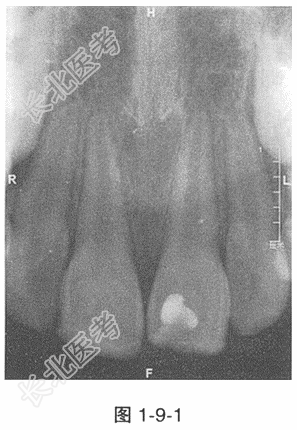

- 多项选择题3.11护髓术、21部分牙髓切断术后1个月随访,若患儿诉进食时11有一过性不适, 11牙髓温度测试冷诊反应较12稍迟缓,X线检查11根尖未见异常(图1-9-1)。11的治疗方案是